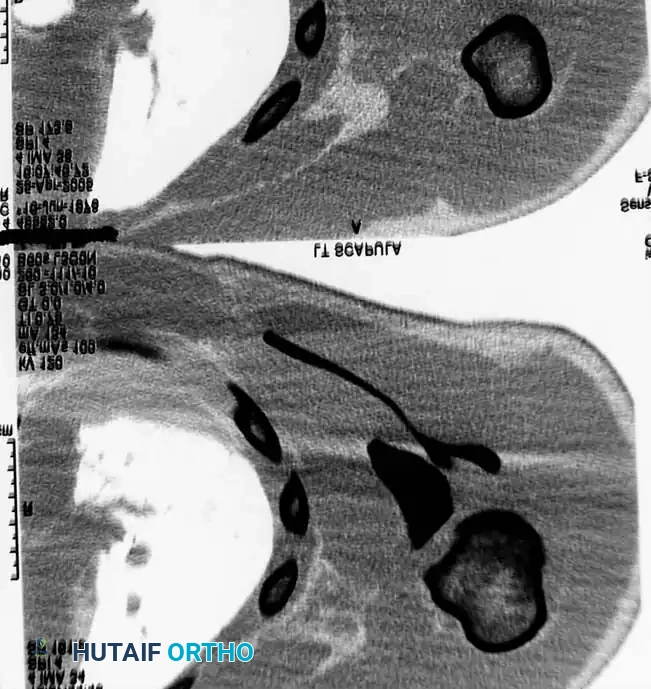

Fig. 54-3B: Axial CT scan detailing the severe displacement of the scapular body and neck.

Fig. 54-3C: Additional axial CT slice confirming intra-articular extension and comminution.